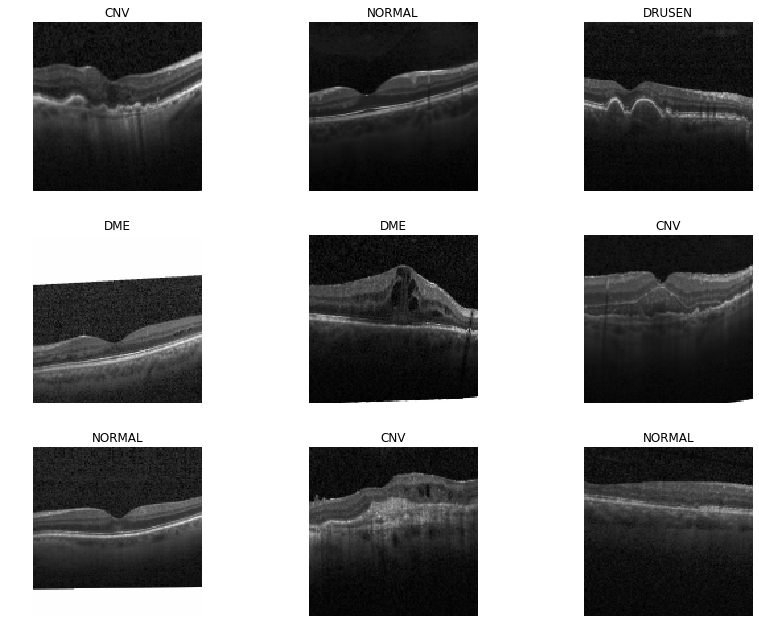

data.show_batch(rows=3, figsize=(12,9))

We’re trying to classify the eyes into one of 4 categories. 1. Healthy 2. Choroidal Neovascularization (blood vessel formation in the eye, related to macular degeneration) 3. Diabetic macular edema (fluid in the retina) 4. Drusen (fat deposits in the retina)